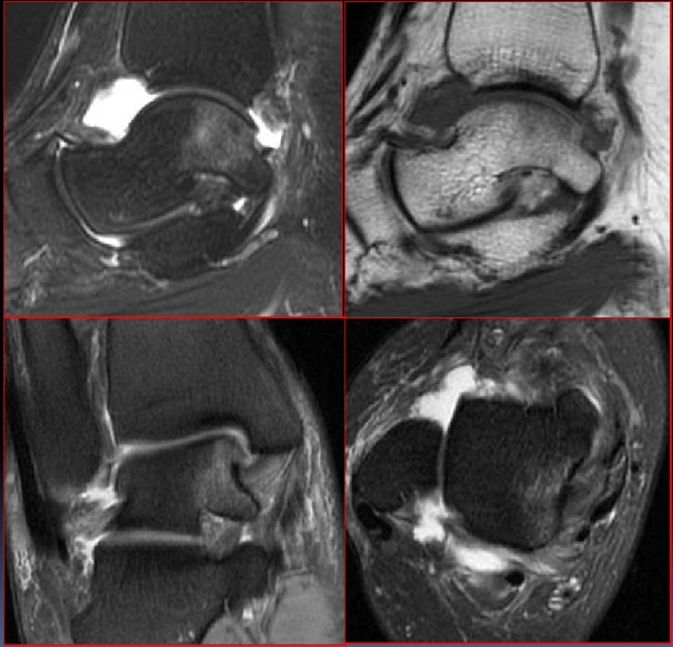

当院のmri 検査 ~分離症~ 腰椎分離症 1 第4腰椎の分離です。 分離部が白くなっています。 (T2) 同左 T1では黒くなっています。 同左 上:T2横断像 下:T1横断像 腰椎分離症 2 第5腰椎の分離です。 分離部が白くなっています。(T2) 同左 T1では黒くなっています。 同左 右に比べ左が白く変化し 腰椎分離すべり症の手術をしました 腰椎分離すべり症とは? 背骨の骨と骨の間にある椎間板(やわらかいジェルのようなもの、骨と骨の間のクッション的なもの)が壊れ、本来きれいに並んでいる背骨が分離してしまい、ずれてしまう症状。 その結果Mri検査:局所の骨髄浮腫を確認し初期分離症の発見を行います。 CT検査: MRI 後、進行度合を判断する目的に行い、 1 回目の CT 検査の後は、骨癒合の経過をみる為に 2 ~ 6 ヵ月後、再度 CT 検査を実

第4腰椎分離症 いしもと整形外科リハビリクリニック 公式 Esaote 日本で唯一の整形領域専用mri